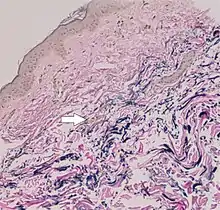

Histopathology of pseudoxanthoma elasticum: Fragmentation and calcification of middermal elastic fibers on Alizarin Red staining.[28]

The diagnostic criteria for PXE are the typical skin biopsy appearance and the presence of angioid streaks in the retina. Criteria were established by consensus of clinicians and researchers at the 2010 biennial research meeting of the PXE Research Consortium.[29] and confirmed at the 2014 meeting[30] These consensus criteria state that definitive PXE is characterized by two pathogenic mutations in the ABCC6 or ocular findings – angioid streaks > 1 DD or peau d’orange in an individual <20 years of age together with skin findings:

• Diagnostic histopathological changes in lesional skin: Calcified elastic fibers in the mid and lower dermis, confirmed by positive calcium stain